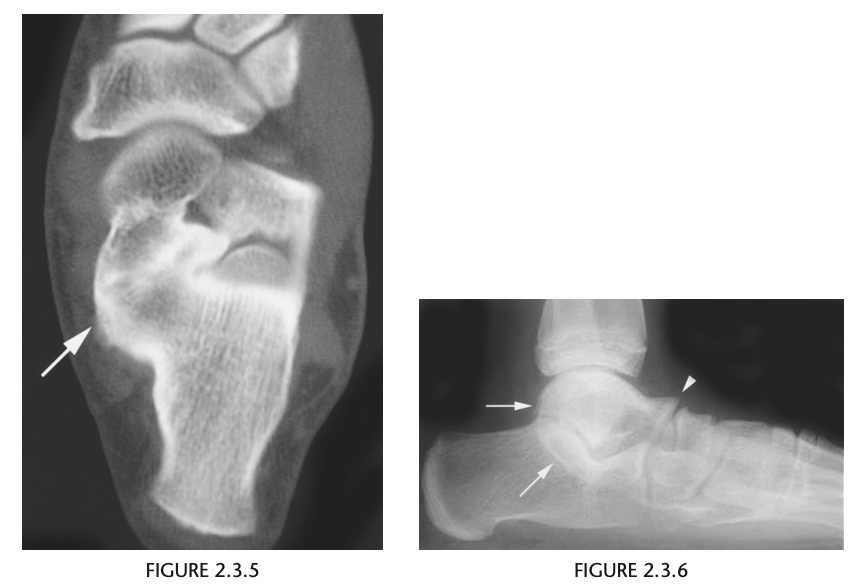

A lateral radiograph of the left foot demonstrates a prominent talar beak

­ (arrow) and bony sclerosis overlying the middle

facet (arrowheads). Coronal CT through the middle

facet shows talocalcaneal fusion, with bony bridging between the talus and the sustentaculum tali of the

calcaneus

Diagnosis: Tarsal coalition

abnormal fusion

of one or more of the tarsal bones, may be fibrous,

cartilaginous, or osseous and may be posttraumatic, or congenital.

Most

common tarsal coalitions are calcaneonavicular and

talocalcaneal.

Radiographically, calcaneonavicular coalition may

be suspected because of elongation of the anterior

facet of the calcaneus on radiographs (i.e., anteater

sign. CT can also be used to confirm coalition and shows

­ sclerosis at the articulation

Congenital coalition usually evolves from fibrous to osseous

coalition and may not be apparent on the initial

evaluation

Talocalcaneal coalition can result in dorsal beaking

of the talar head (Fig. 2.3.6, arrowhead), the so-called

C-sign (arrows)